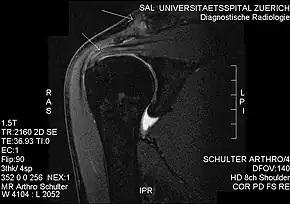

Impingement syndrome can be diagnosed by a targeted medical history and physical examination,[11][12] but it has also been argued that at least medical imaging[13] (generally X-ray initially) and/or response to local anesthetic injection[14] is necessary for workup. However, imaging studies are unable to show cause of shoulder pain in diagnosing. For example, MRI imaging would show rotator cuff pathology and bursitis but is unable to specify the cause.[15]

Plain x-rays of the shoulder can be used to detect some joint pathology and variations in the bones, including acromioclavicular arthritis, variations in the acromion, and calcification. However, x-rays do not allow visualization of soft tissue and thus hold a low diagnostic value.[2] Ultrasonography, arthrography and MRI can be used to detect rotator cuff muscle pathology. MRI is the best imaging test prior to arthroscopic surgery.[2] Due to lack of understanding of the pathoaetiology, and lack of diagnostic accuracy in the assessment process by many physicians,[19] several opinions are recommended before intervention.